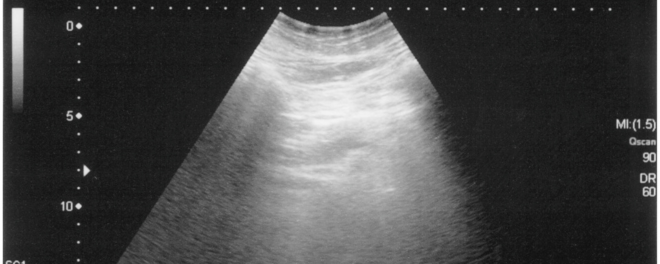

Pelvic ultrasound scan

Evaluates the uterus and ovaries for fibroids, cysts, or other issues.

Ultrasound Imaging

A transvaginal or pelvic ultrasound may be recommended to evaluate:

• Ovarian cysts commonly associated with PCOS

• Uterine fibroids or endometrial irregularities

• Ovulation patterns and endometrial lining thickness